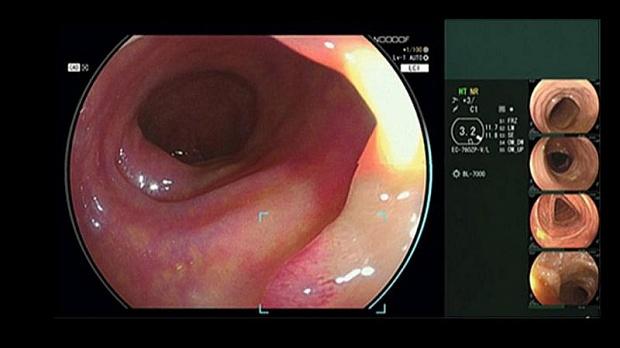

Компания FUJIFILM разработала новую технологию, которая во время колоноскопических исследований способна в режиме реального времени автоматически обнаруживать подозрительные полипы. Технология называется CAD EYE и состоит из аппаратных и программных компонентов, совместимых с эндоскопической системой ELUXEO 7000 этой же компании.

Фирма надеется, что CAD EYE, который автоматически включается в разных режимах визуализации - в режиме белого света (White Light) и в режиме LCI (Linked Colour Imaging), обеспечивает соответствие самым высоким требованиям в отношении яркости и контрастности. Такая технология может помочь повысить точность обнаружения образований (полипов) и уменьшить нагрузку на врачей, выполняющих множество ежедневных процедур.

Для удобства и простоты использования был разработан удобный интерфейс, который не мешает эндоскопическому изображению и сводит к минимуму движение глаз оператора. При обнаружении подозрительного полипа в эндоскопическом изображении блок обнаружения системы указывает область, в которой был обнаружен подозрительный полип, а в непосредственной близости загорается зрительный вспомогательный круг. Кроме того, при обнаружении подозрительного полипа раздается звуковой сигнал.